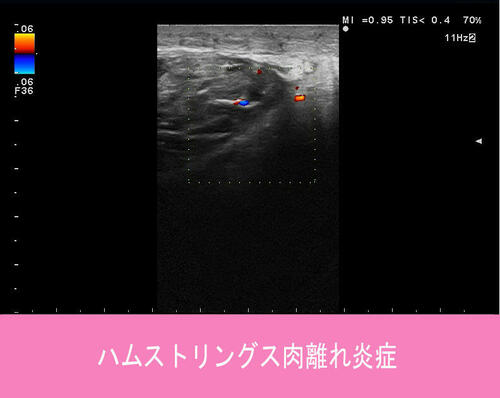

筋肉から腱に移行する部分で、炎症反応、低エコー像が診られます。

ハムストリングス肉離れ炎症.jpg